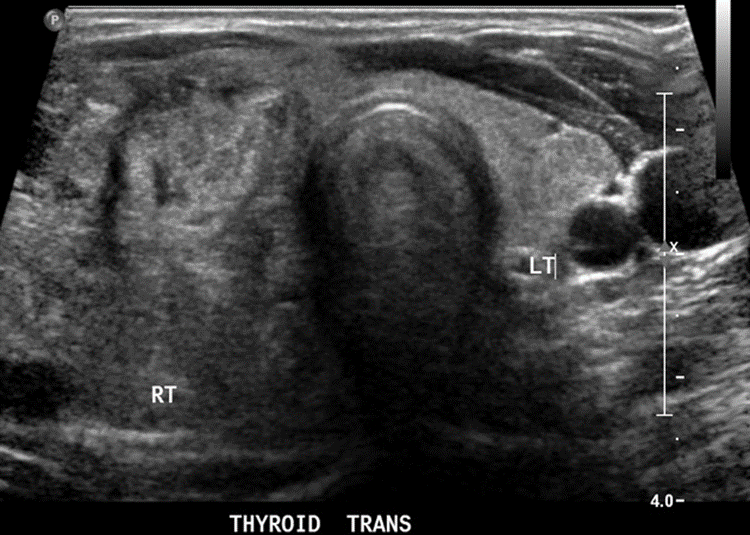

Thyroid ultrasound:

Multiple nodules within the thyroid parenchyma.